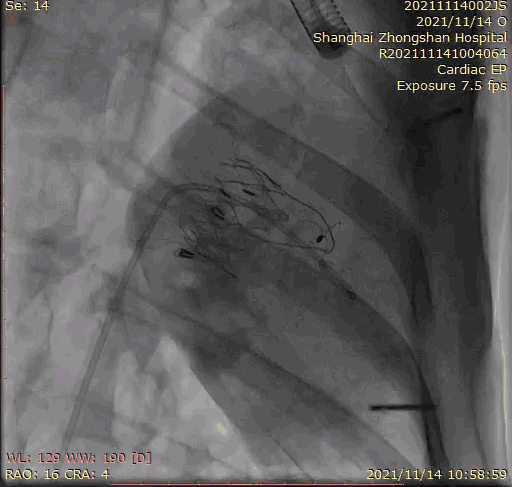

2021年11月14日星期日,復旦大學附屬中山醫院(以下簡稱中山醫院)葛均波院士團隊成功應用經血管介入三尖瓣置換產品Lux-Valve Plus完成臨床前研究,并獲得圓滿成功!此次研究的成功預示經血管三尖瓣產品Lux-Valve Plus已完成臨床前準備,即將開啟后期的正式臨床研究!

上海中山醫院葛均波院士、錢菊英院長、周達新教授、潘文志教授、潘翠珍教授、李偉教授共同完成此次臨床前研究。術后葛均波院士對Lux-Valve Plus的器械操作性能給予了高度評價,DSA和超聲影像也顯示出在本次研究中Lux-Valve Plus的安全性和有效性俱佳。

本次臨床前研究經右側頸靜脈置入LuX-Valve Plus輸送系統可調彎鞘管,在DSA及超聲引導下將人工三尖瓣瓣膜植入到原有三尖瓣位置,利用獨特的錨定技術將人工瓣膜支架可靠固定在預定的位置。